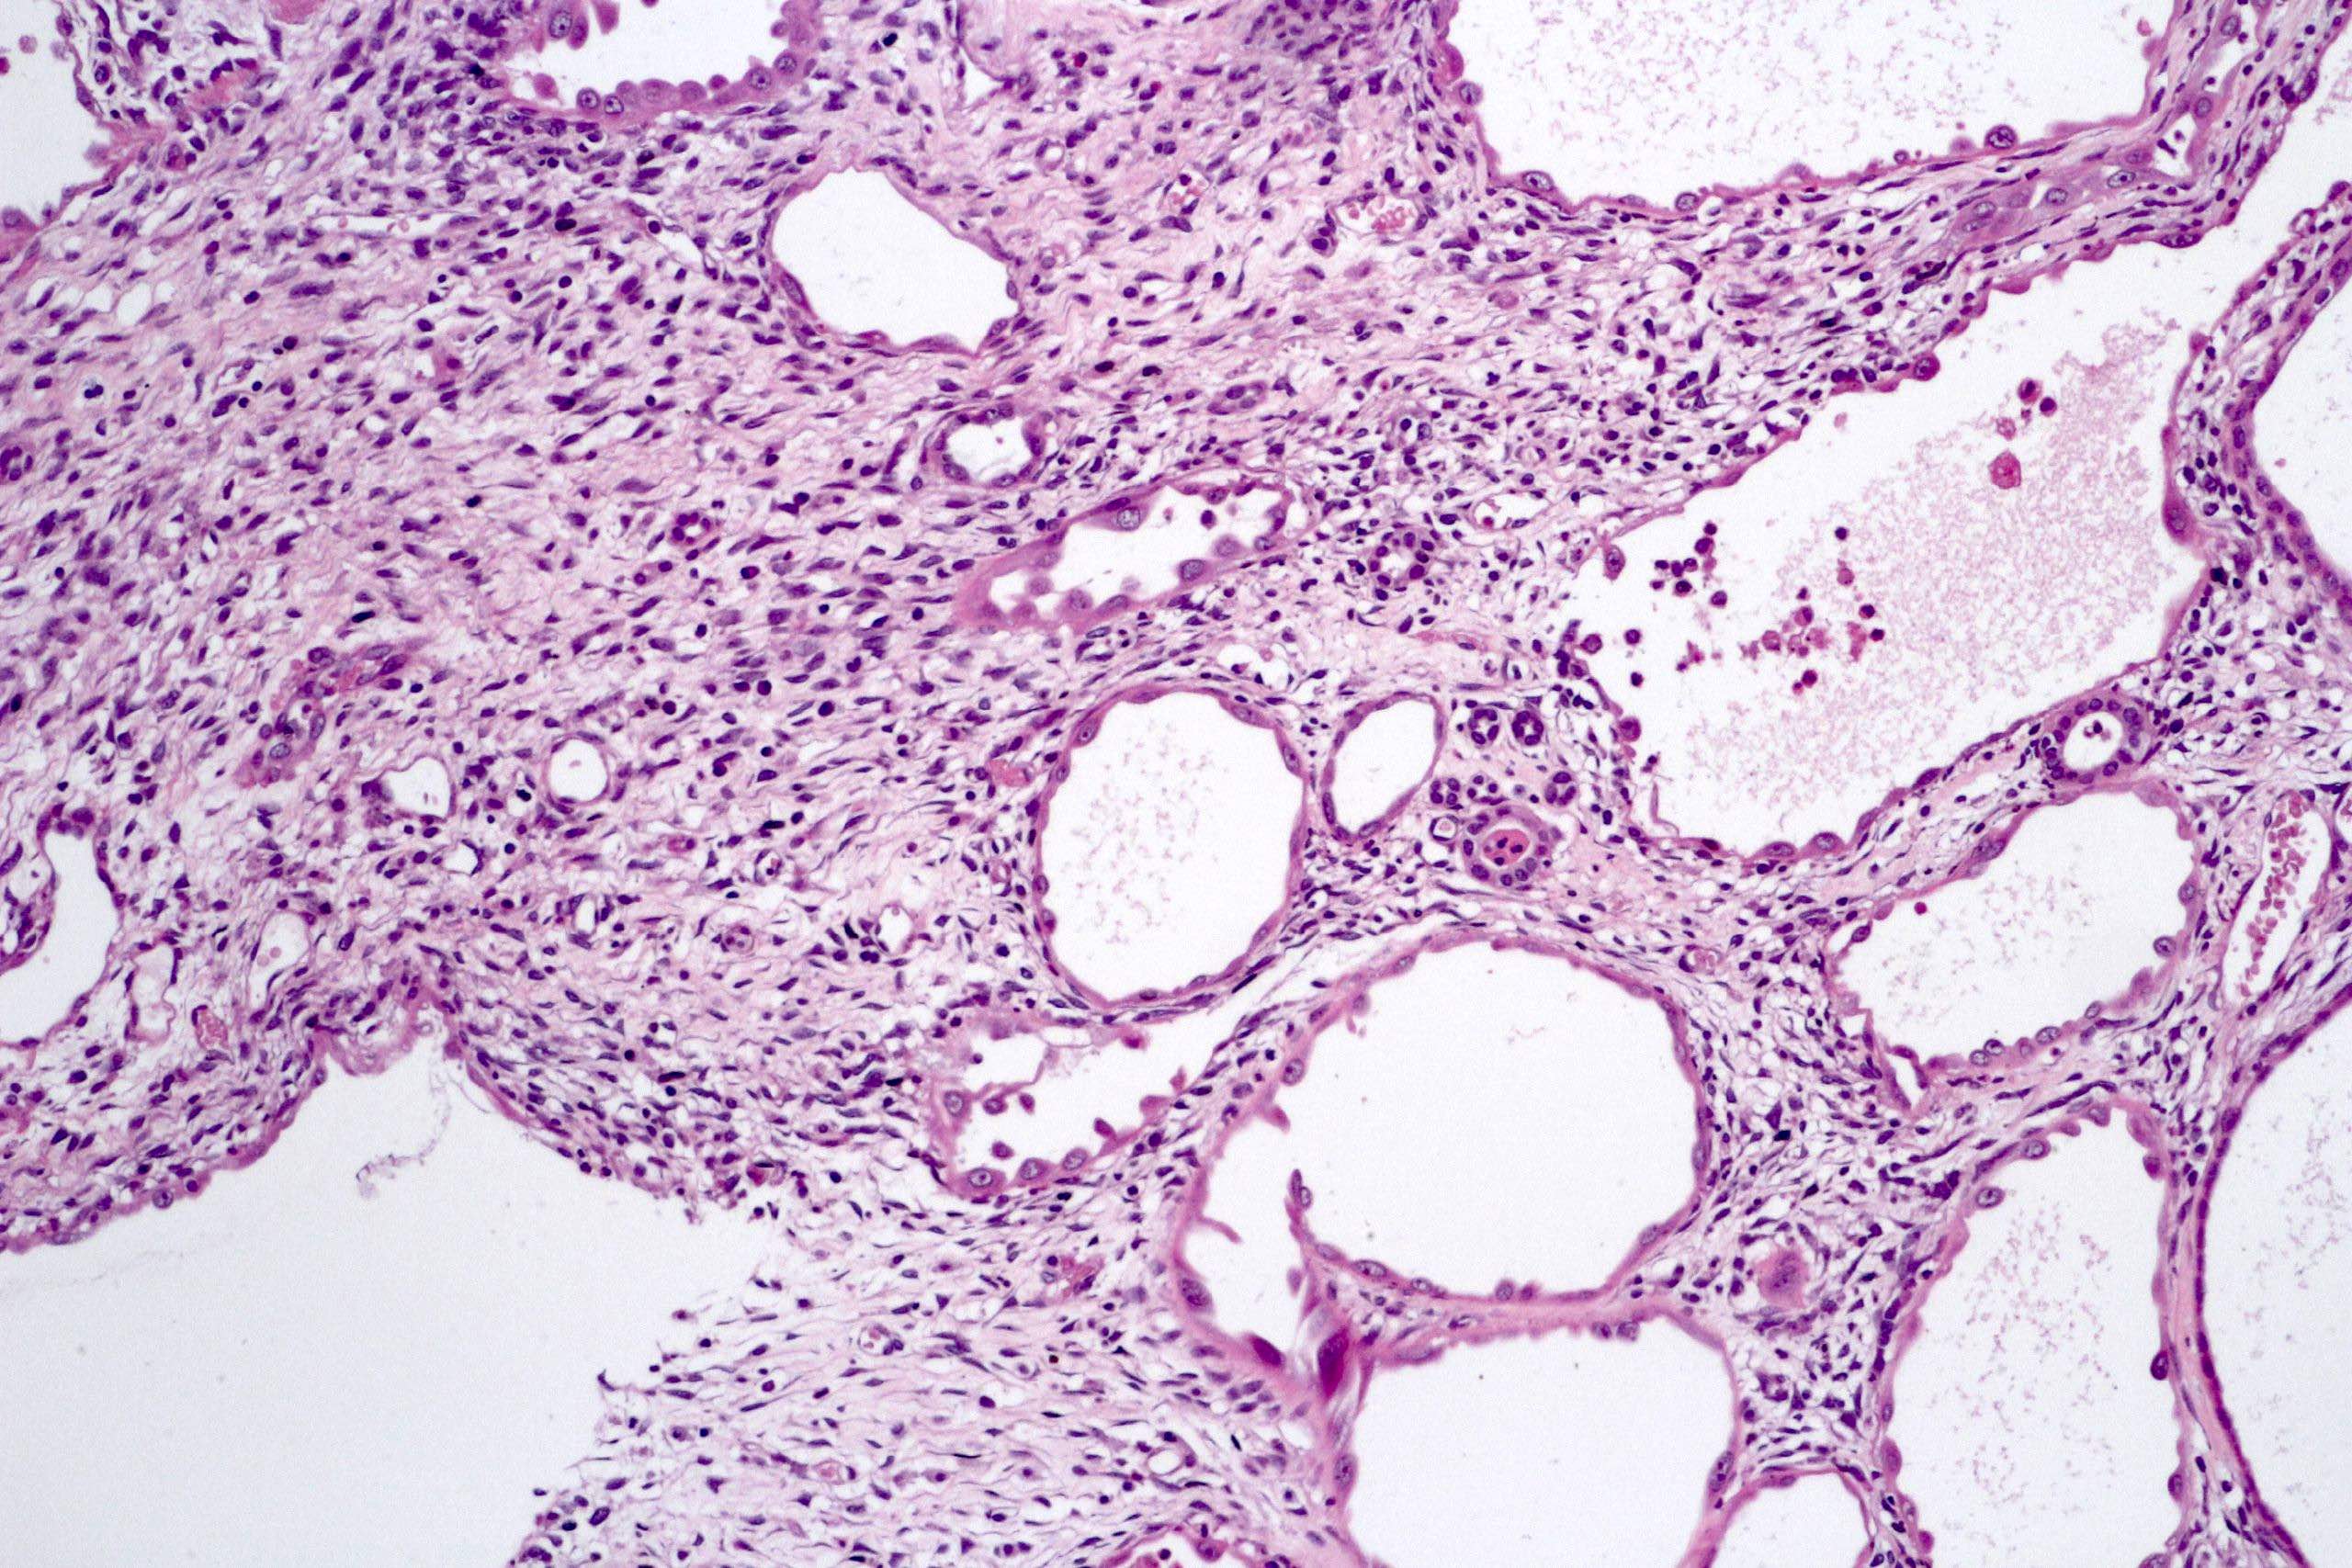

Microscopic (histologic) description

- Cysts lined with flat / cuboidal / hobnail cells (or are denuded)

- Epithelial elements consist mainly of mature and immature / abortive tubules and small papillae resembling immature glomeruli

- Key histological findings of the variably cellular septa include

- Nephroblastomatous epithelial elements

- Islands of undifferentiated blastema and differentiated mesenchymal elements (skeletal muscle and less often cartilage and fat) (J Urol 2010;183:1585)

- Focally, the septal elements may protrude into the cystic spaces in microscopic papillary folds

Microscopic (histologic) images

Contributed by Americo Brilhante, M.D. and Daniel Athanazio, M.D., Ph.D.